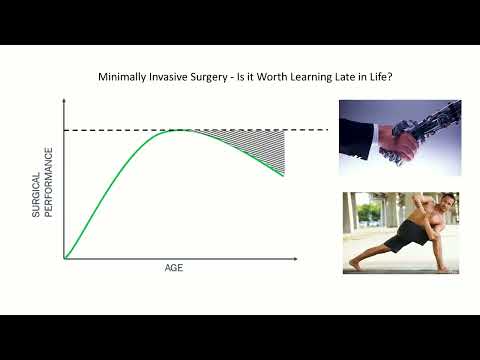

DEB06 Minimally Invasive Surgery - Is it Worth Learning Late in Life? Yes/No

Debate 06: Minimally Invasive Surgery - Is it Worth Learning Late in Life? Yes/No